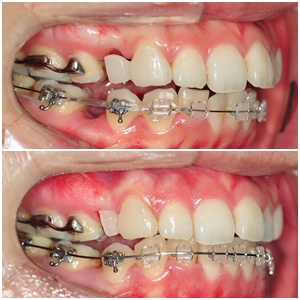

첫번째 월치료 받았을 때 사진이랑 일곱번째 월치료 받았을 때 사진 비교해서 올려 볼께요 ^^

└▷ 처음 바이트블록 붙였을 때는 상악/하악 치아공간이 많이 띄어져 있었는데~

지금은 많이 낮아졌어요~ 처음 바이트블록 붙였을 때의 어색함이 생각난다는.. ㅋㅋ

혼자 방황하던 하악 앞니 하나도 가지런 해지고~ 신나신나~ ^^

└▷ 발치공간이 줄어들 수록 임시치아 크기도 같이 줄어듭니다~ (깍아서 빈 공간을 만들어 주기 때문에~!)

이렇게 비교해서 보니 임시치아 크기도 많이 줄었네요 ㅋㅋ 하악 발치공간도 많이 줄었구요~

└▷ 하악 앞니는 삐뚤삐뚤했던 처음에 비해 많이 가지런해졌고~

발치공간도 눈에 띄게 많이 줄었어요~! ^^ 얼른 닫히길 바라며~~ ㅋㅋ

└▷ 옆모습입니다~!! 인중부분과 입술아래부분 각도가 달라졌어요 + _+)b

와ㅇㅏ~ 돌출입이 쭉쭉 잘 들어가고 있군요 ^^ㅋㅋ 정말 감동입니다~ ㅠㅠ